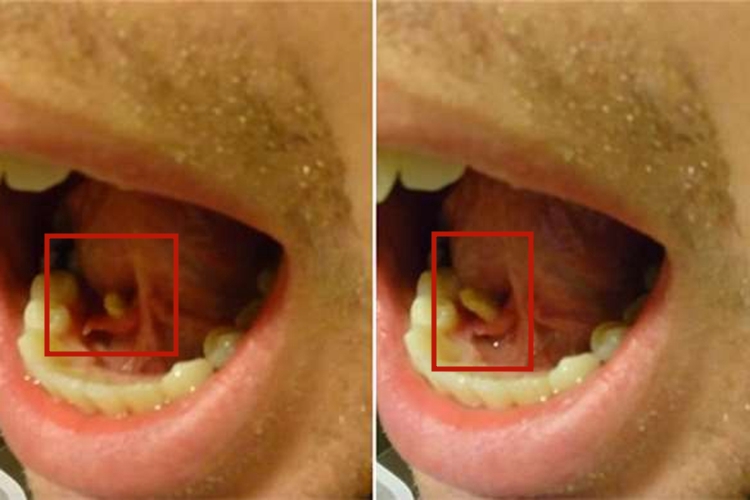

尖锐湿疣

可表现为单个或多个毛刺状增生物或无痛性疣状结节,有蒂或无蒂,可逐渐增大或融合,形成菜花状或乳头状,颜色正常或苍白色,患者可有异物感。